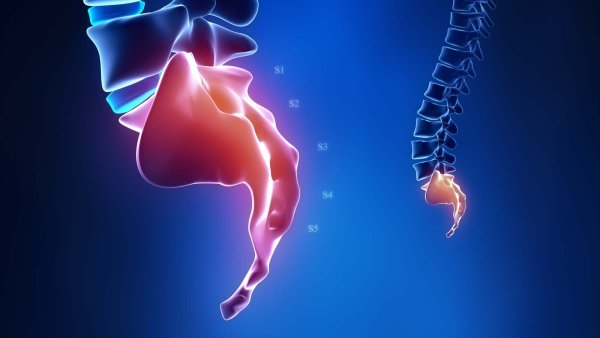

Miecha a miechové nervové korene

Miecha sa oddelí zo spodnej časti mozgu, prebieha skrz krčnú a hrudnú chrbticu a končí v dolnej časti hrudnej chrbtice. Preto úrazy alebo poškodenia miechy môžu byť sprevádzané traumou alebo… Viac

6 príznakov spinálnej stenózy

Spinálna stenóza nastáva, keď sa kostné otvory pre vaše miechové nervy (foramen) a/alebo miecha (centrálny kanál) zúžia. Toto zúženie môže stlačiť miechu a/alebo miechové nervy a môže sa vyvinúť na… Viac

Všetko o segmente chrbtice L4-L5

L4 a L5 sú dva najnižšie stavce bedrovej chrbtice. Spolu s medzistavcovými platničkami, kĺbmi, nervami a mäkkými tkanivami poskytuje pohybový segment chrbtice L4-L5 rôzne funkcie, vrátane podpory… Viac